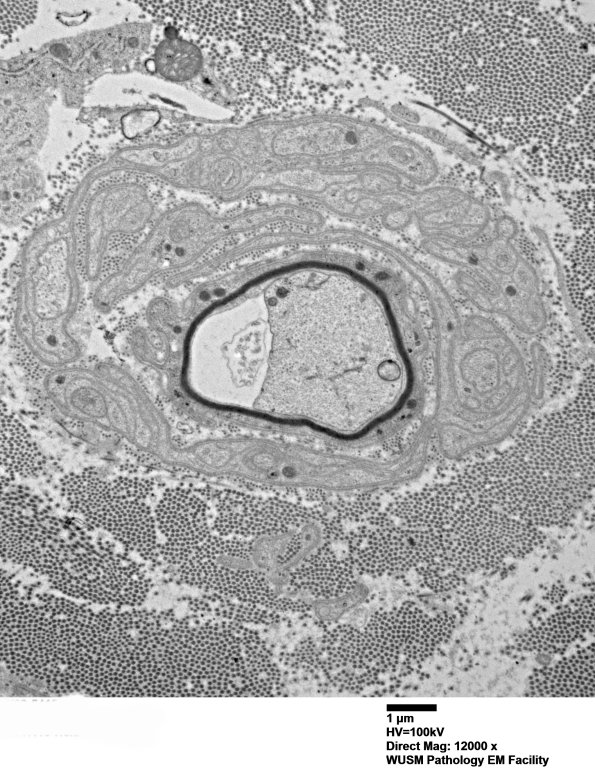

Remyelination of a small axon with a hint of concentric Schwann processes forming an “onion-bulb”. (electron micrographs)